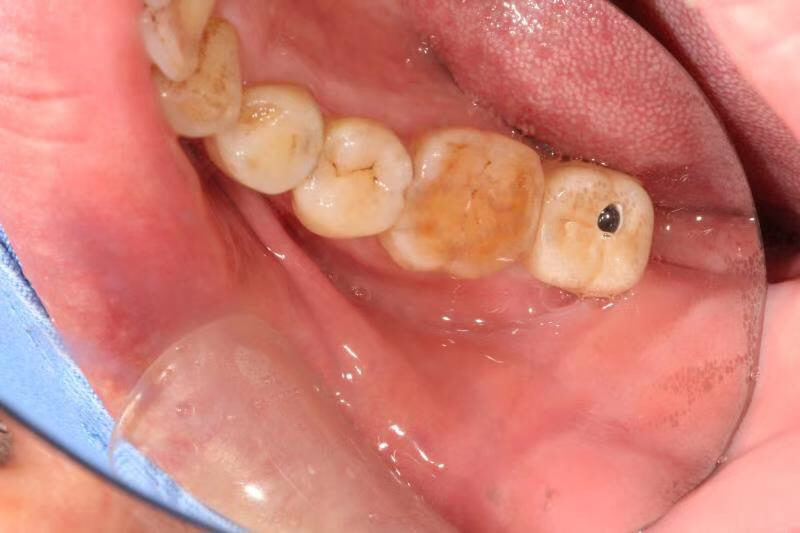

今天给大家介绍一个单颗后牙即拔即种病例。

患者中年男性,右下7号牙龋坏未及时处理至残根无法修复,CT检查发现骨量尚可,可以即拔即种,并且不需要植骨,节省了患者治疗周期,整个治疗过程用了4个月患者就戴上了牙齿。